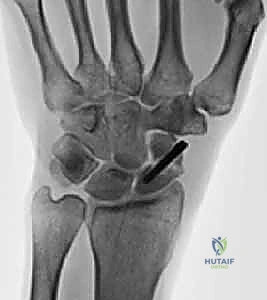

- الأشعة السينية الرقمية (Digital X-rays): بأوضاع متعددة (AP, Lateral, Scaphoid view) لتقييم زوايا العظام ودرجة الانهيار.

- الأشعة المقطعية (CT Scan): وهي المعيار الذهبي لتقييم حجم العظم المتآكل بدقة ثلاثية الأبعاد، وتحديد مدى الخشونة في المفاصل المحيطة.

- الاستئصال الدقيق: باستخدام أدوات جراحية ميكروسكوبية دقيقة، يتم استئصال حوالي 3 إلى 4 مليمترات من القطب البعيد للعظم الزورقي. هذه الكمية كافية لمنع الاحتكاك مع عظم الكعبرة، وفي نفس الوقت تحافظ على استقرار الأربطة.